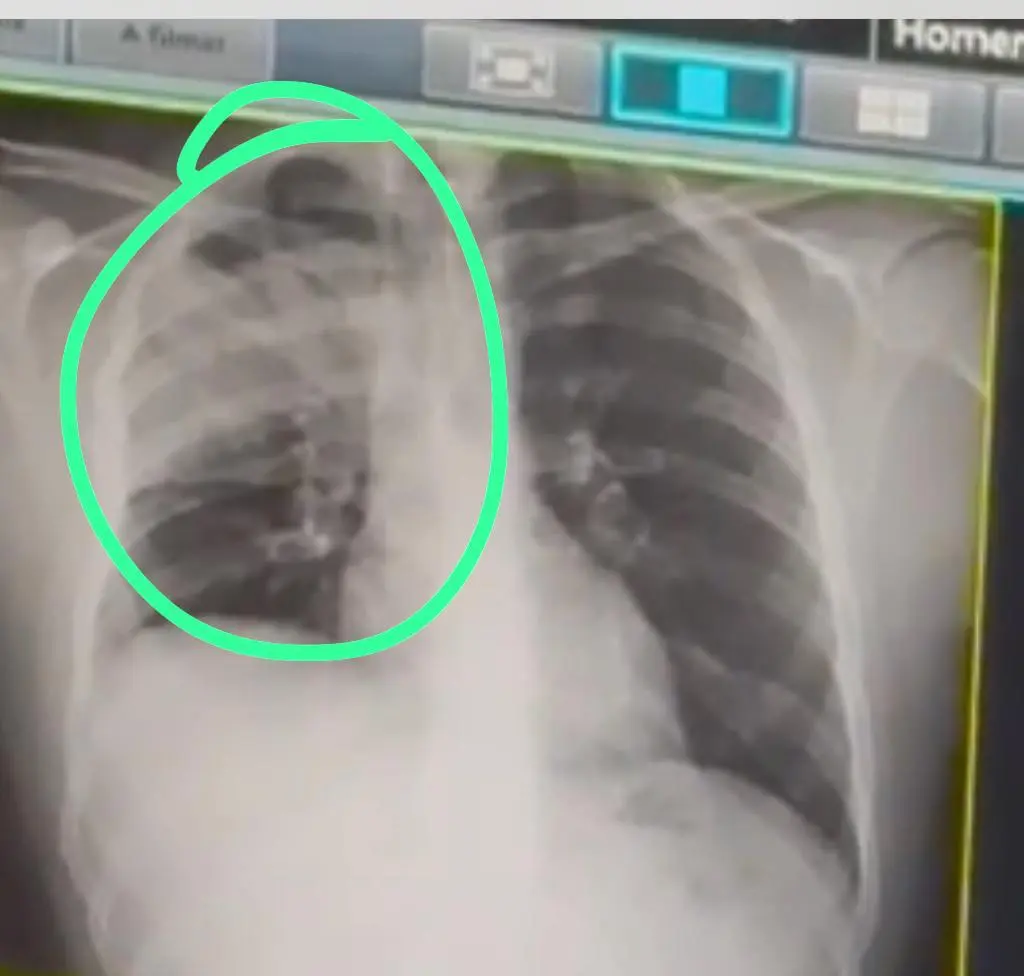

Drudi descreveu a experiência: “Semana passada, do nada, comecei a ficar ruim. Senti uma dor no meio do meu pulmão e aí fui pro hospital com a minha amiga. Quando cheguei lá, o médico disse que meu pulmão estava do lado direito bem comprometido e já me internaram com pneumonia. Estava com a bactéria, por conta do uso do vaper, direto”.

“O médico disse que meu pulmão estava do lado direito bem comprometido e já me internaram com pneumonia, estava com a bactéria”, disse ao ContilNet.